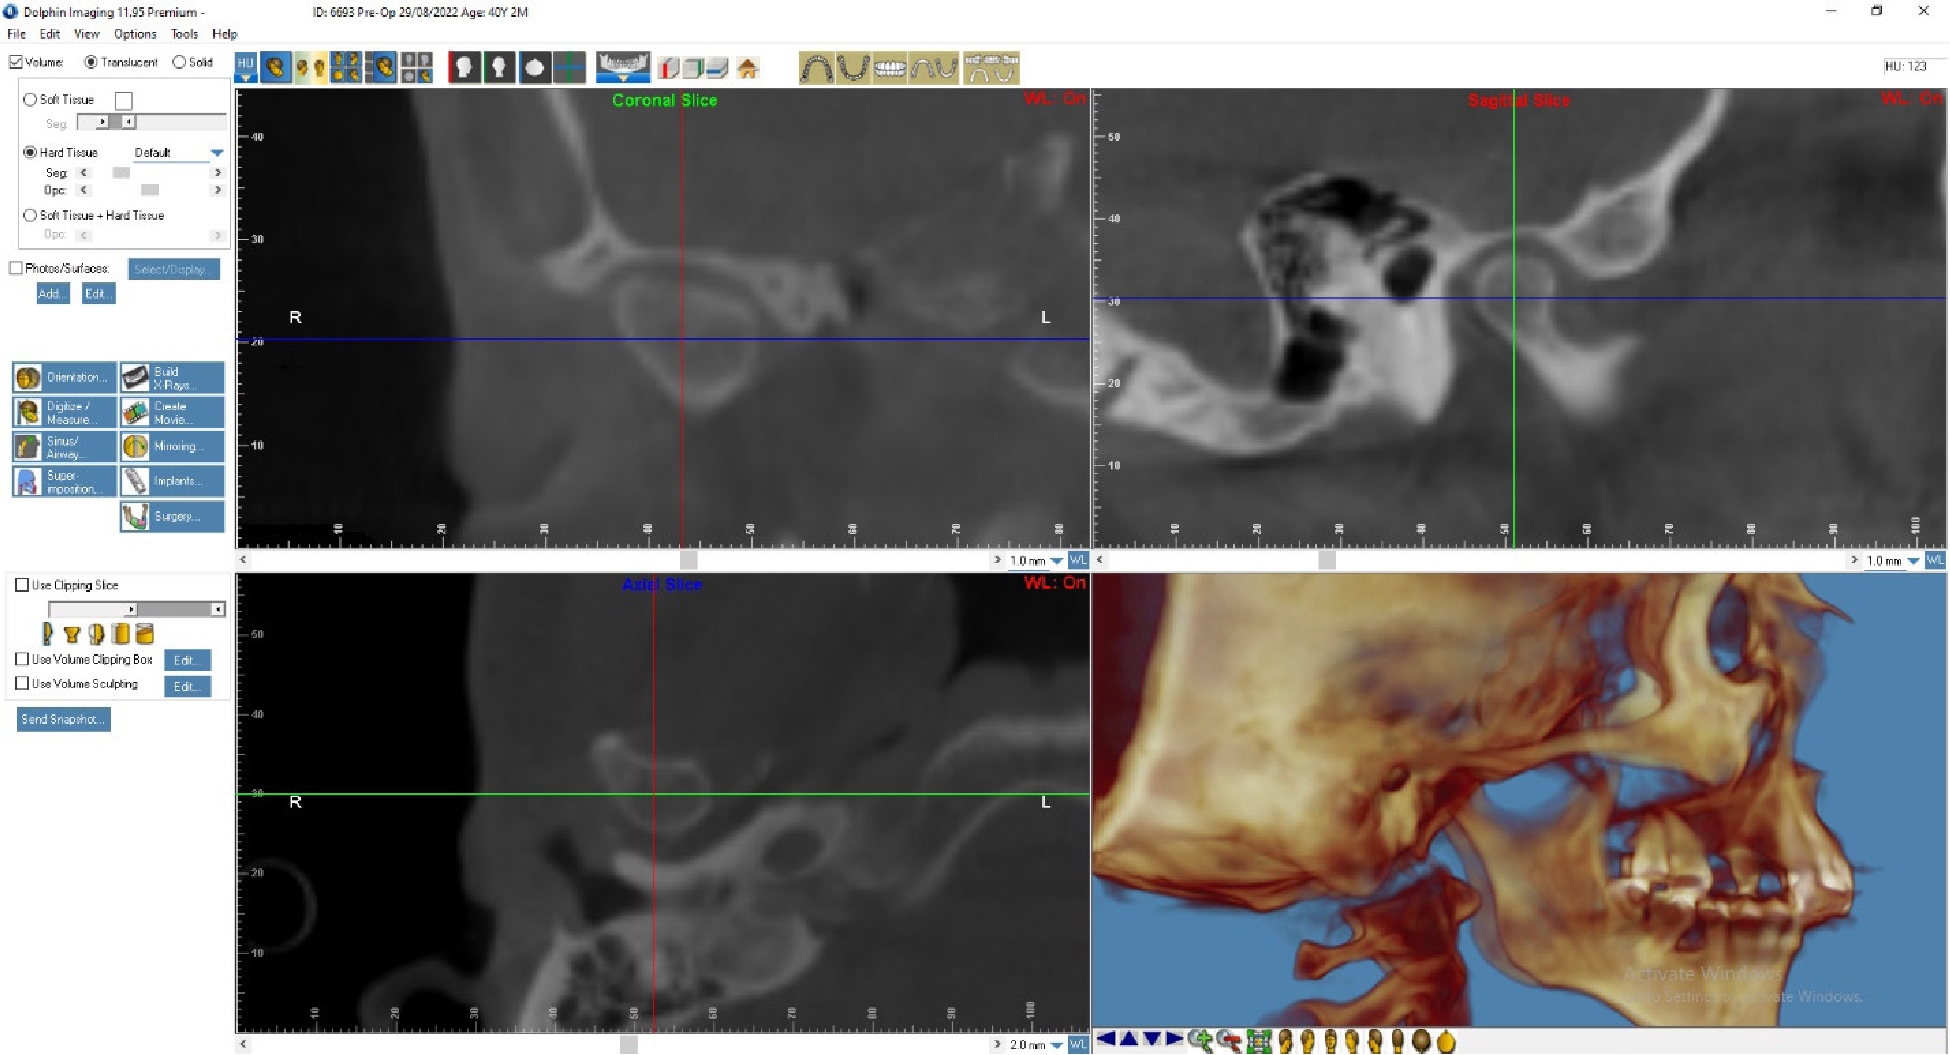

На основании КТ с использованием лицензионной программы Dolphin Imaging 11.95 Premium определяли цефалометрические параметры черепа и анатомические изменения в ВНЧС. Для интерпретации результатов МРТ использовали Radiant Dicom Viewer.

По данным МРТ ВНЧС спустя 2 года после начала лечения отмечается устранение вентро-латеральной дислокации суставного диска в положении привычной окклюзии. Также устранен синовит, увеличился объем движения в суставе (рис. 5). Как видно из рис. 4 и 5, по данным КТ ВНЧС спустя 2 года после начала лечения отмечается ремоделирование головки нижней челюсти. Клинически увеличилось открывание рта до 38 мм.

Рис. 5. Пациент Д., 40 лет. КТ ВНЧС спустя 2 года после начала лечения